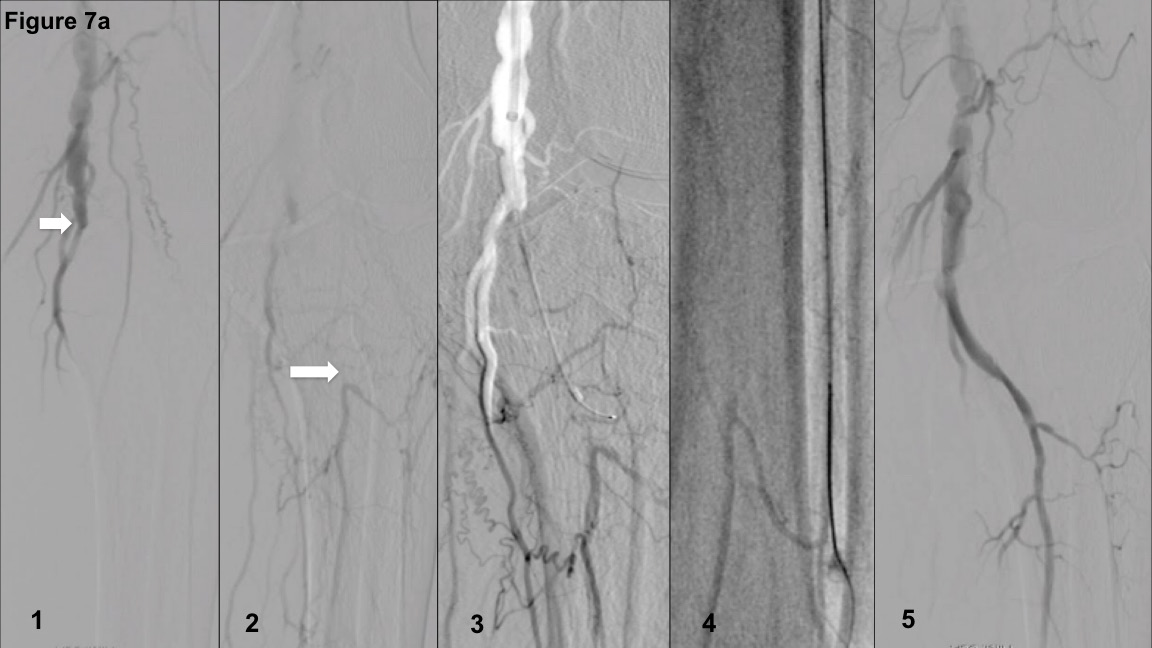

Figure 7A-Panel 1 represents a distal popliteal artery BTK-PCTO lesion in a patient with CLI. The lesion is classified as type IIIB based on a tapered proximal cap and PCTO length between 50-150 mm and an ambiguous distal cap (Figure 7A-Panel 2). Based on these features, an initial antegrade crossing with a .014˝ Hi Torque Command guidewire (Abbott Vascular) supported within a compatible straight-tip catheter was selected. The entry of the guidewire into the subintimal space (Figure 7A-Panel 3) was followed by retrograde anterior tibial artery access and Confianza Pro 12 guidewire (Asahi Intecc) entry into the antegrade true lumen following RCART (the hybrid approach, shown in Figure 7A-Panels 4 and 5).